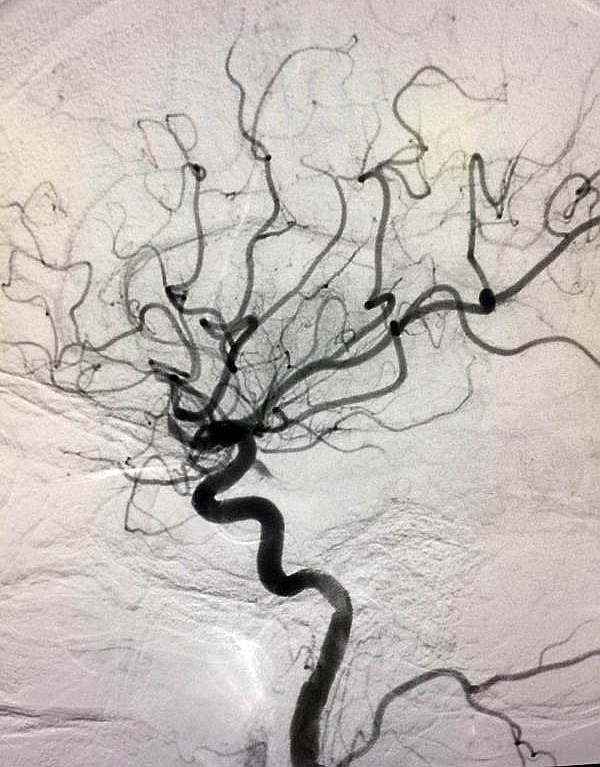

第二幅:還是那棵樹,經(jīng)過辛勤園丁的治療、搶救,這棵樹恢復(fù)了年輕時的繁華。您瞧,枯樹發(fā)出了新芽,進(jìn)而枝繁葉茂,煥發(fā)出了勃勃生機(jī)和活力。多么令人振奮的畫面啊!不僅令我想起了一句話——生命之樹常綠!

其實(shí),這兩幅畫并非人工繪制,而是來自濱州市人民醫(yī)院介入手術(shù)室血管造影機(jī)拍攝的影像。

經(jīng)過兩個小時的緊張手術(shù),20:30分手術(shù)完成,取出了大量的腦部血栓。患者雙側(cè)瞳孔等大,對光反射存在,直接2mm,觀察30分鐘,血流通暢,返回病房。晚上9:30,患者神志清醒,語言交流正常,右側(cè)肌力2級。